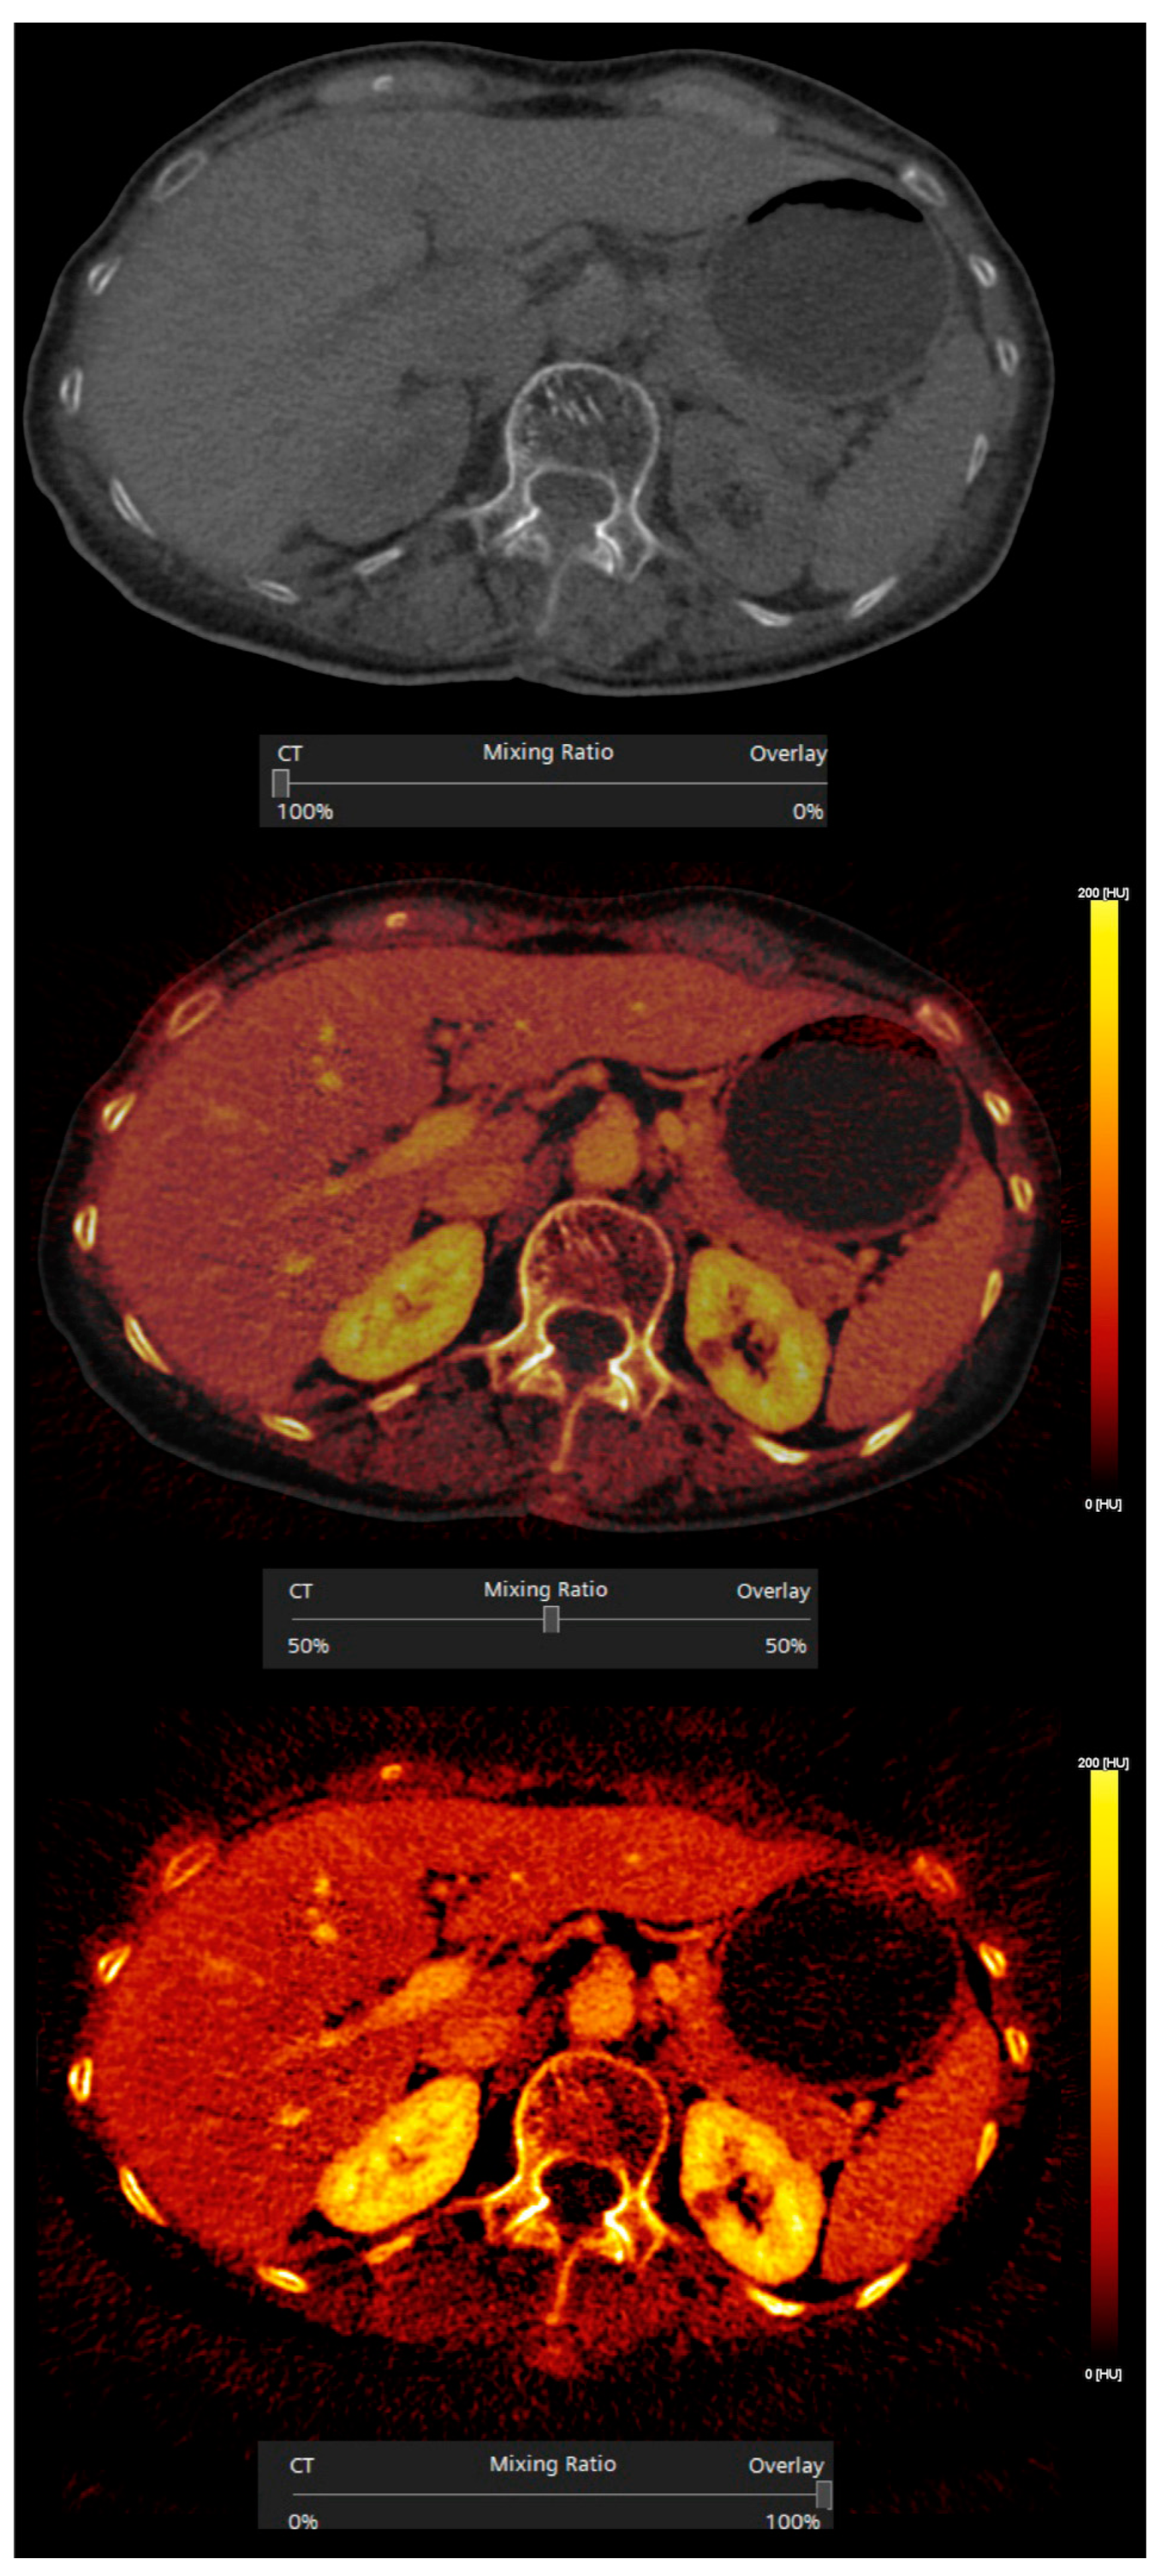

3.1. Postprocessing Techniques